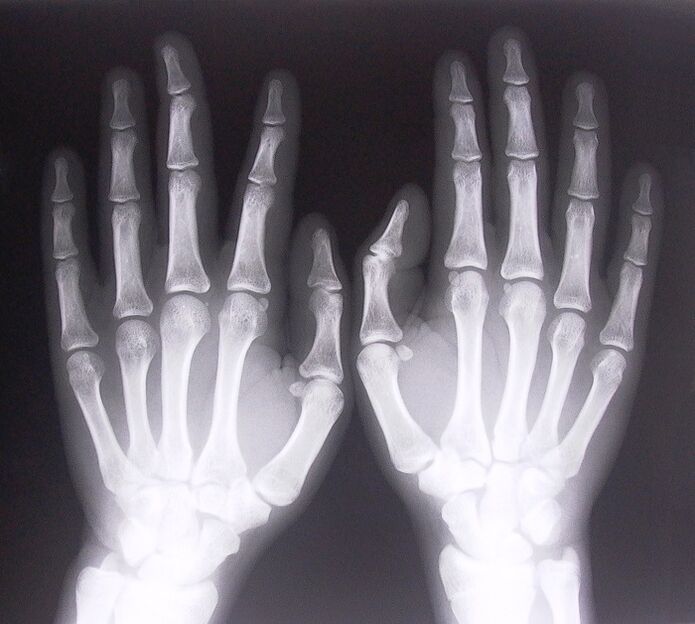

- Stenotic ligamentitis.To determine the cause of the disease, it is necessary to undergo an X-ray examination.Symptoms are characteristic: painful movement of the hand, compressed palm loops.Also, clicks are usually heard during expansion.

To start treating joint pain in the fingers, you need to correctly determine what disease is causing them.To determine what kind of disease a person who feels pain in the joints when bending his arms, doctors recommend to undergo the following procedures:

- Take X-rays.

- Get a CT scan.

- Get an MRI.